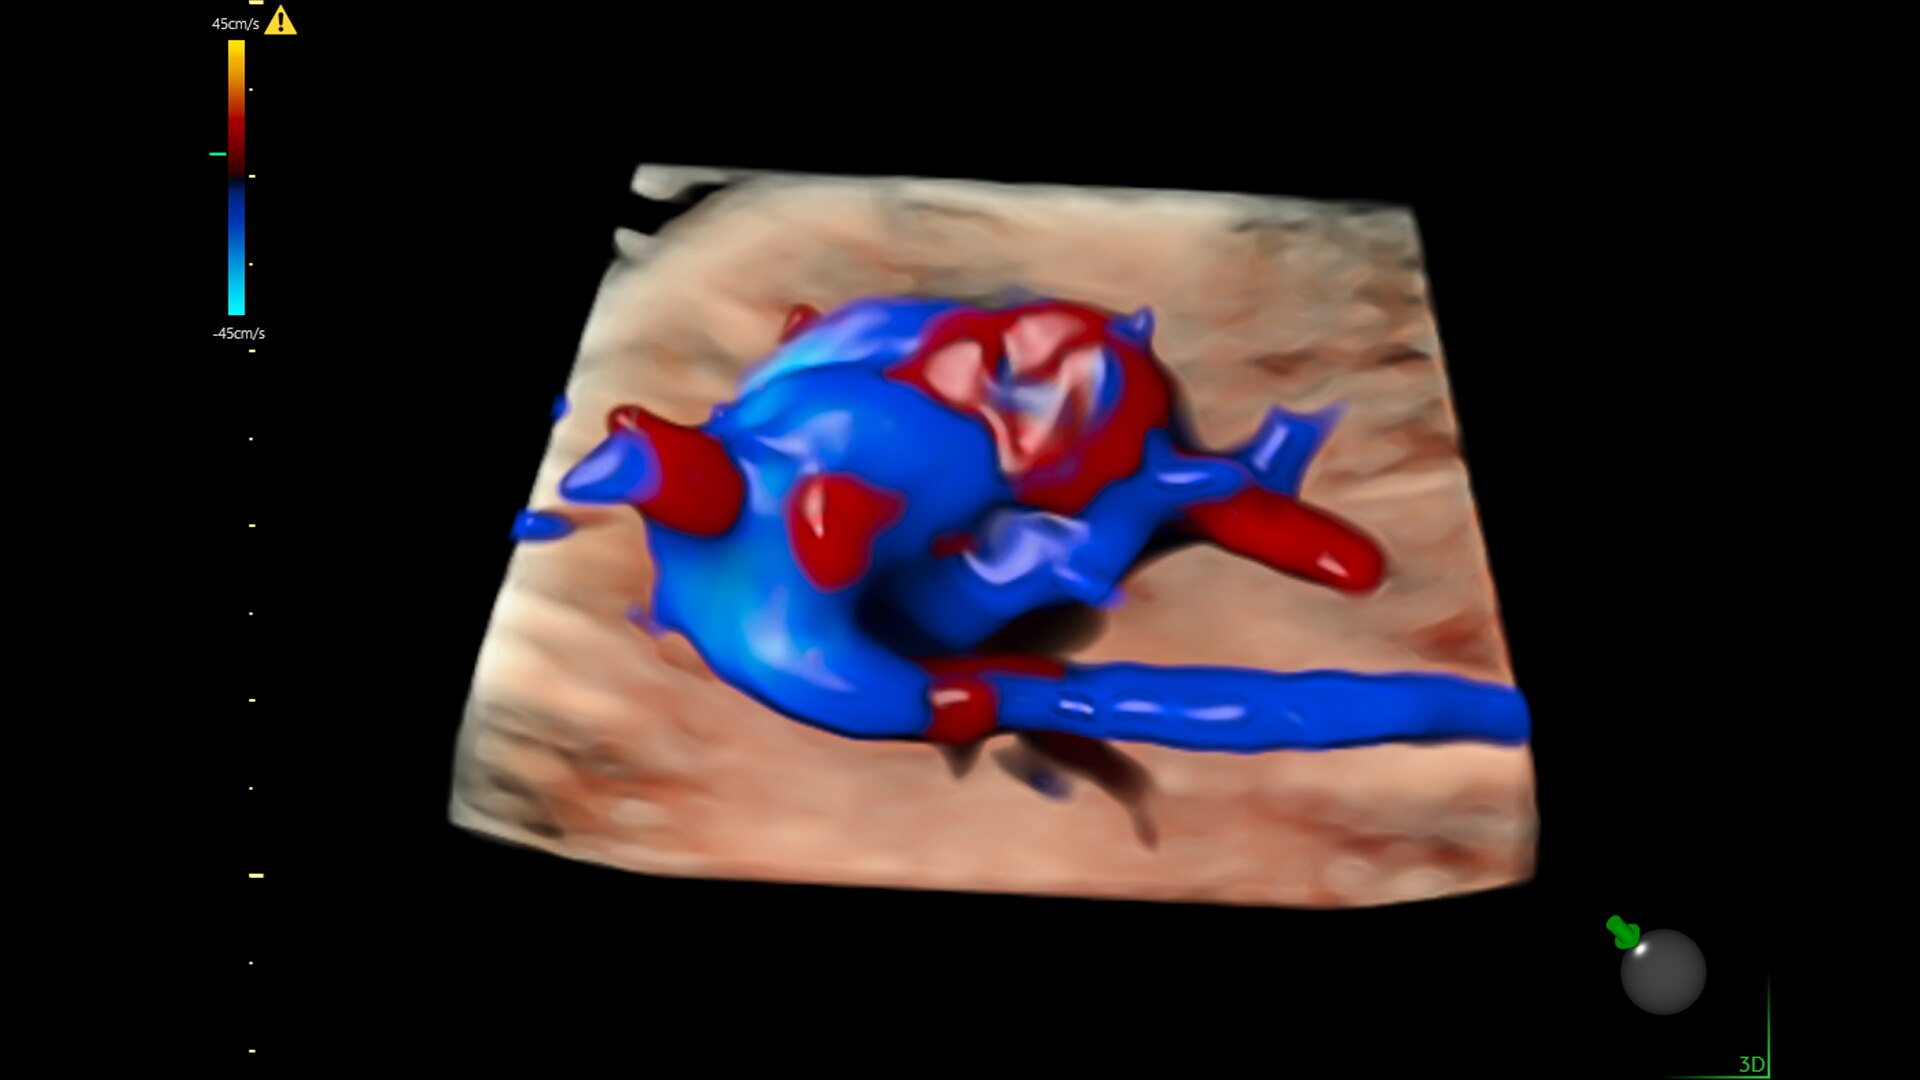

Fast, easy 3D-like blood flow visualization

Next level color Doppler that delivers exceptional sensitivity for easy, fast visualization of blood flow, displaying a 3D like appearance as seen in this 27-week fetal heart.